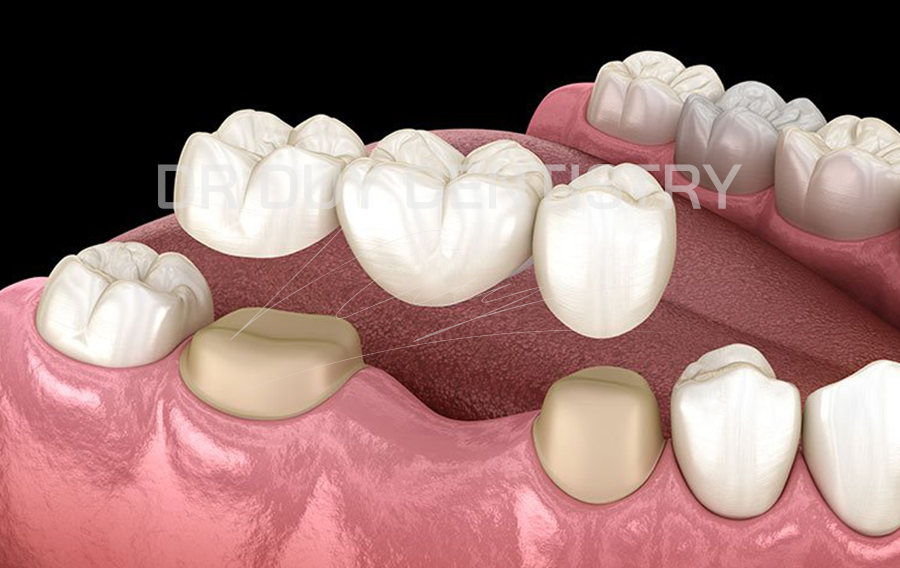

Cầu răng:

Cầu răng là phương pháp thay thế nếu khách hàng không được chỉ định cấy ghép implant hoặc không muốn cấy ghép implant. Đây cũng có thể được sử dụng như phương pháp phục hồi tạm thời đến khi đủ điều kiện cấy ghép implant.